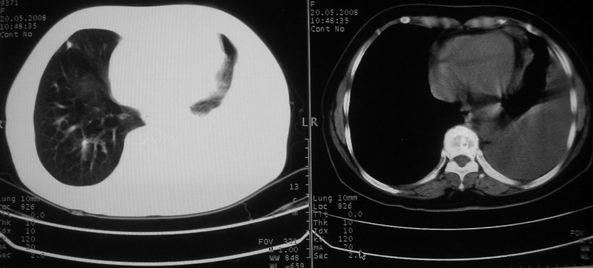

以下是引用w_jianhua在2008-5-22 12:59:00的发言:[br]1.左肺上叶肺癌并左侧胸腔积液可能性大。2不除外支气管内膜结核并包裹性胸腔积液,建议支气管镜检3.左肺下叶肺大泡,肺气肿